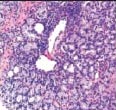

Der Prostatakrebs ist die häufigste bösartige Tumorerkrankung bei Männern.

Diese Erkrankung stellt außerdem die häufigste Todesursache infolge bösartiger Tumore bei Männern dar.

Die rechtzeitige Früherkennung und Behandlung des Prostatakrebses im Rahmen der urologischen Krebsvorsorge sind daher von allergrößter Bedeutung.